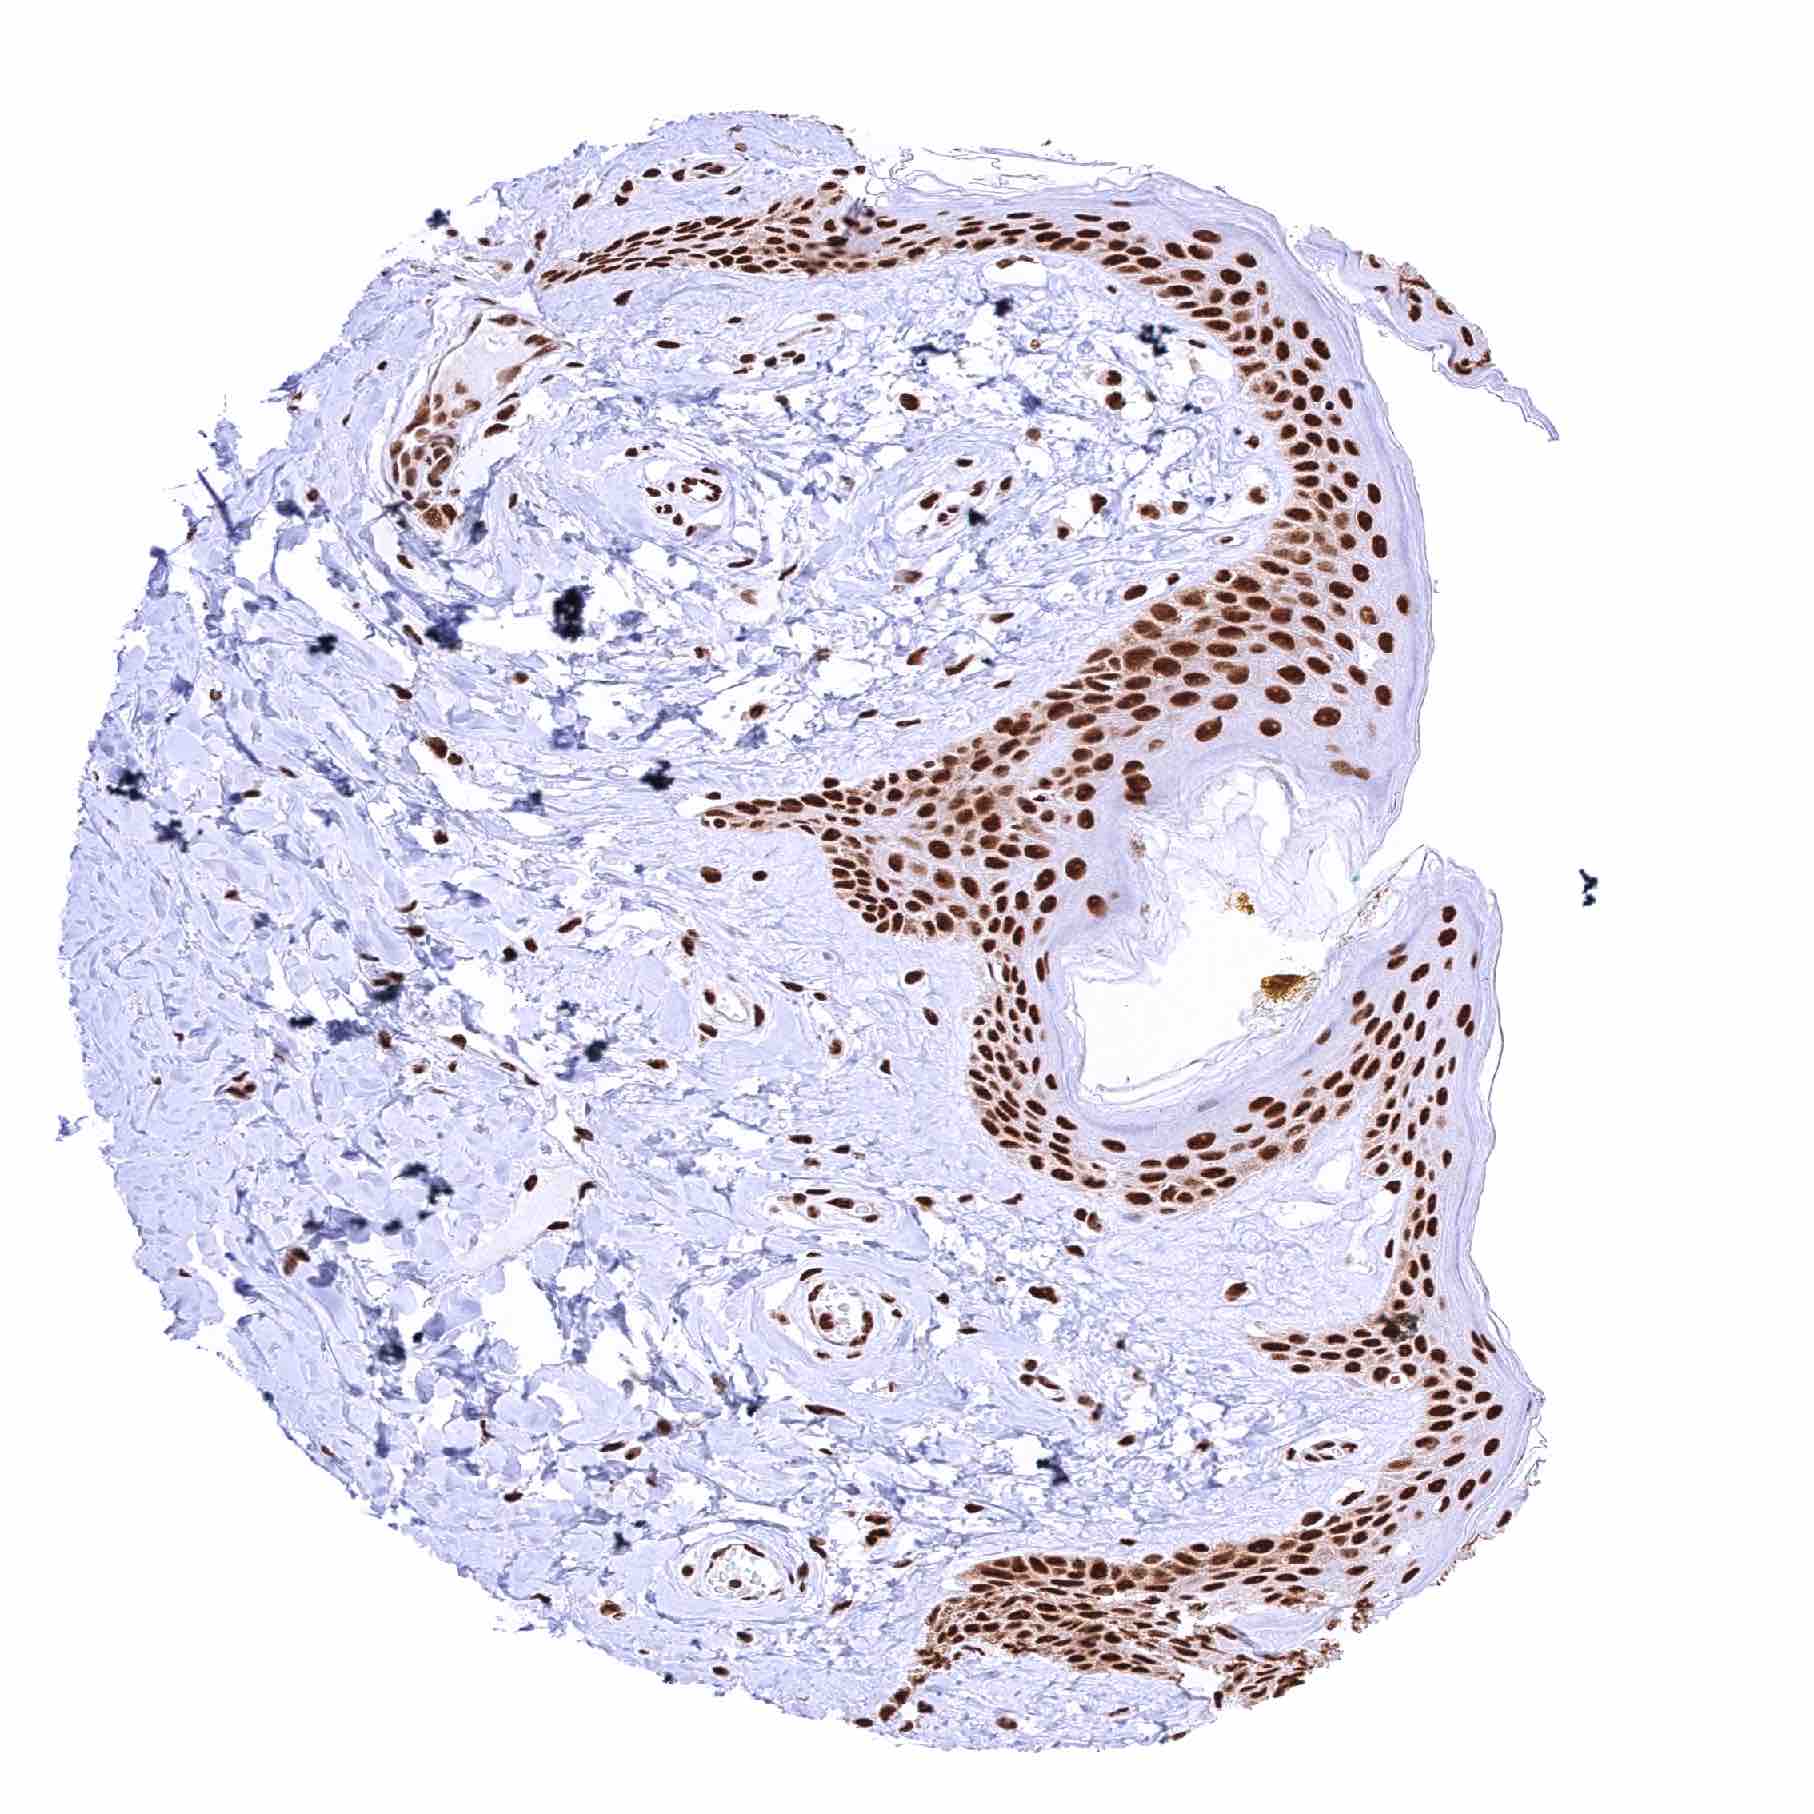

Esophagus, squamous epithelium – Slight but significant decrease of MRE11 staining from the basal-suprabasal to the superficial cell layers of the squamous epithelium